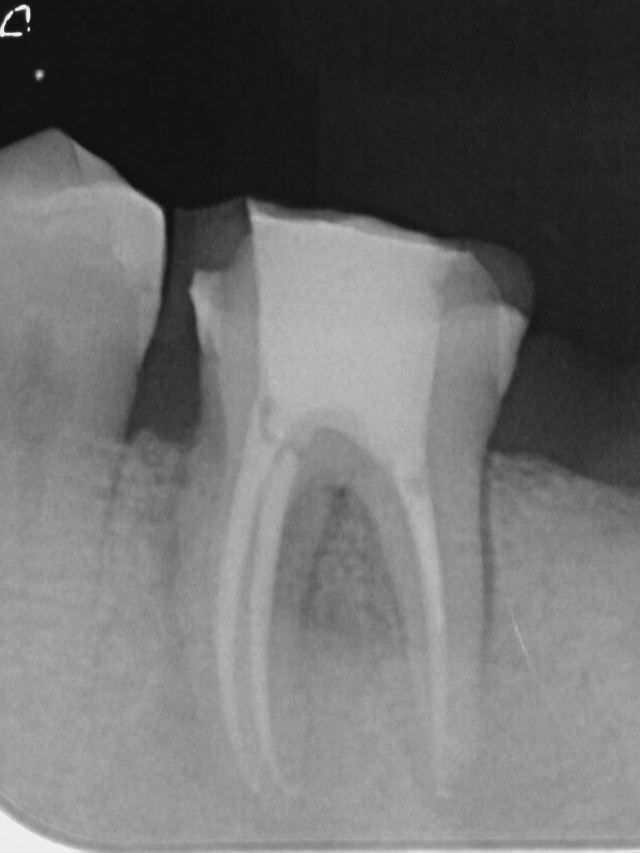

Nah…. masuk kasus pertama, pasien datang dengan keluhan nyeri pada gigi atas kiri nya namun tidak nampak adanya ciri-ciri karies, bahkan beberapa dokter gigi sebelumnya tidak melihat ada yang bermasalah.. setelah pemeriksaan perkusi yang positip, pasien saya insntruksi untuk x-ray digital dari VistaScan dari DURR DENTAL tampak adanya penebalan lamina dura dan rongga abses yang terkonfirmasi dengan guttap untuk memastikan arah abses. Pasien selalu mengeluhkan sakit gigi yang menyerupai dengan pulpitis nah begini pemeriksaan klinisnya.

pasang rubber dam dan buka akses saluran akar seperti biasa,,preparasi menggunakan Protaper Next dari Dentsply sampai X2 irigasi NaOCL 5 % diakhir dengan EDTA 17%

kontrol 1 bulan

kontrol 6 bulan